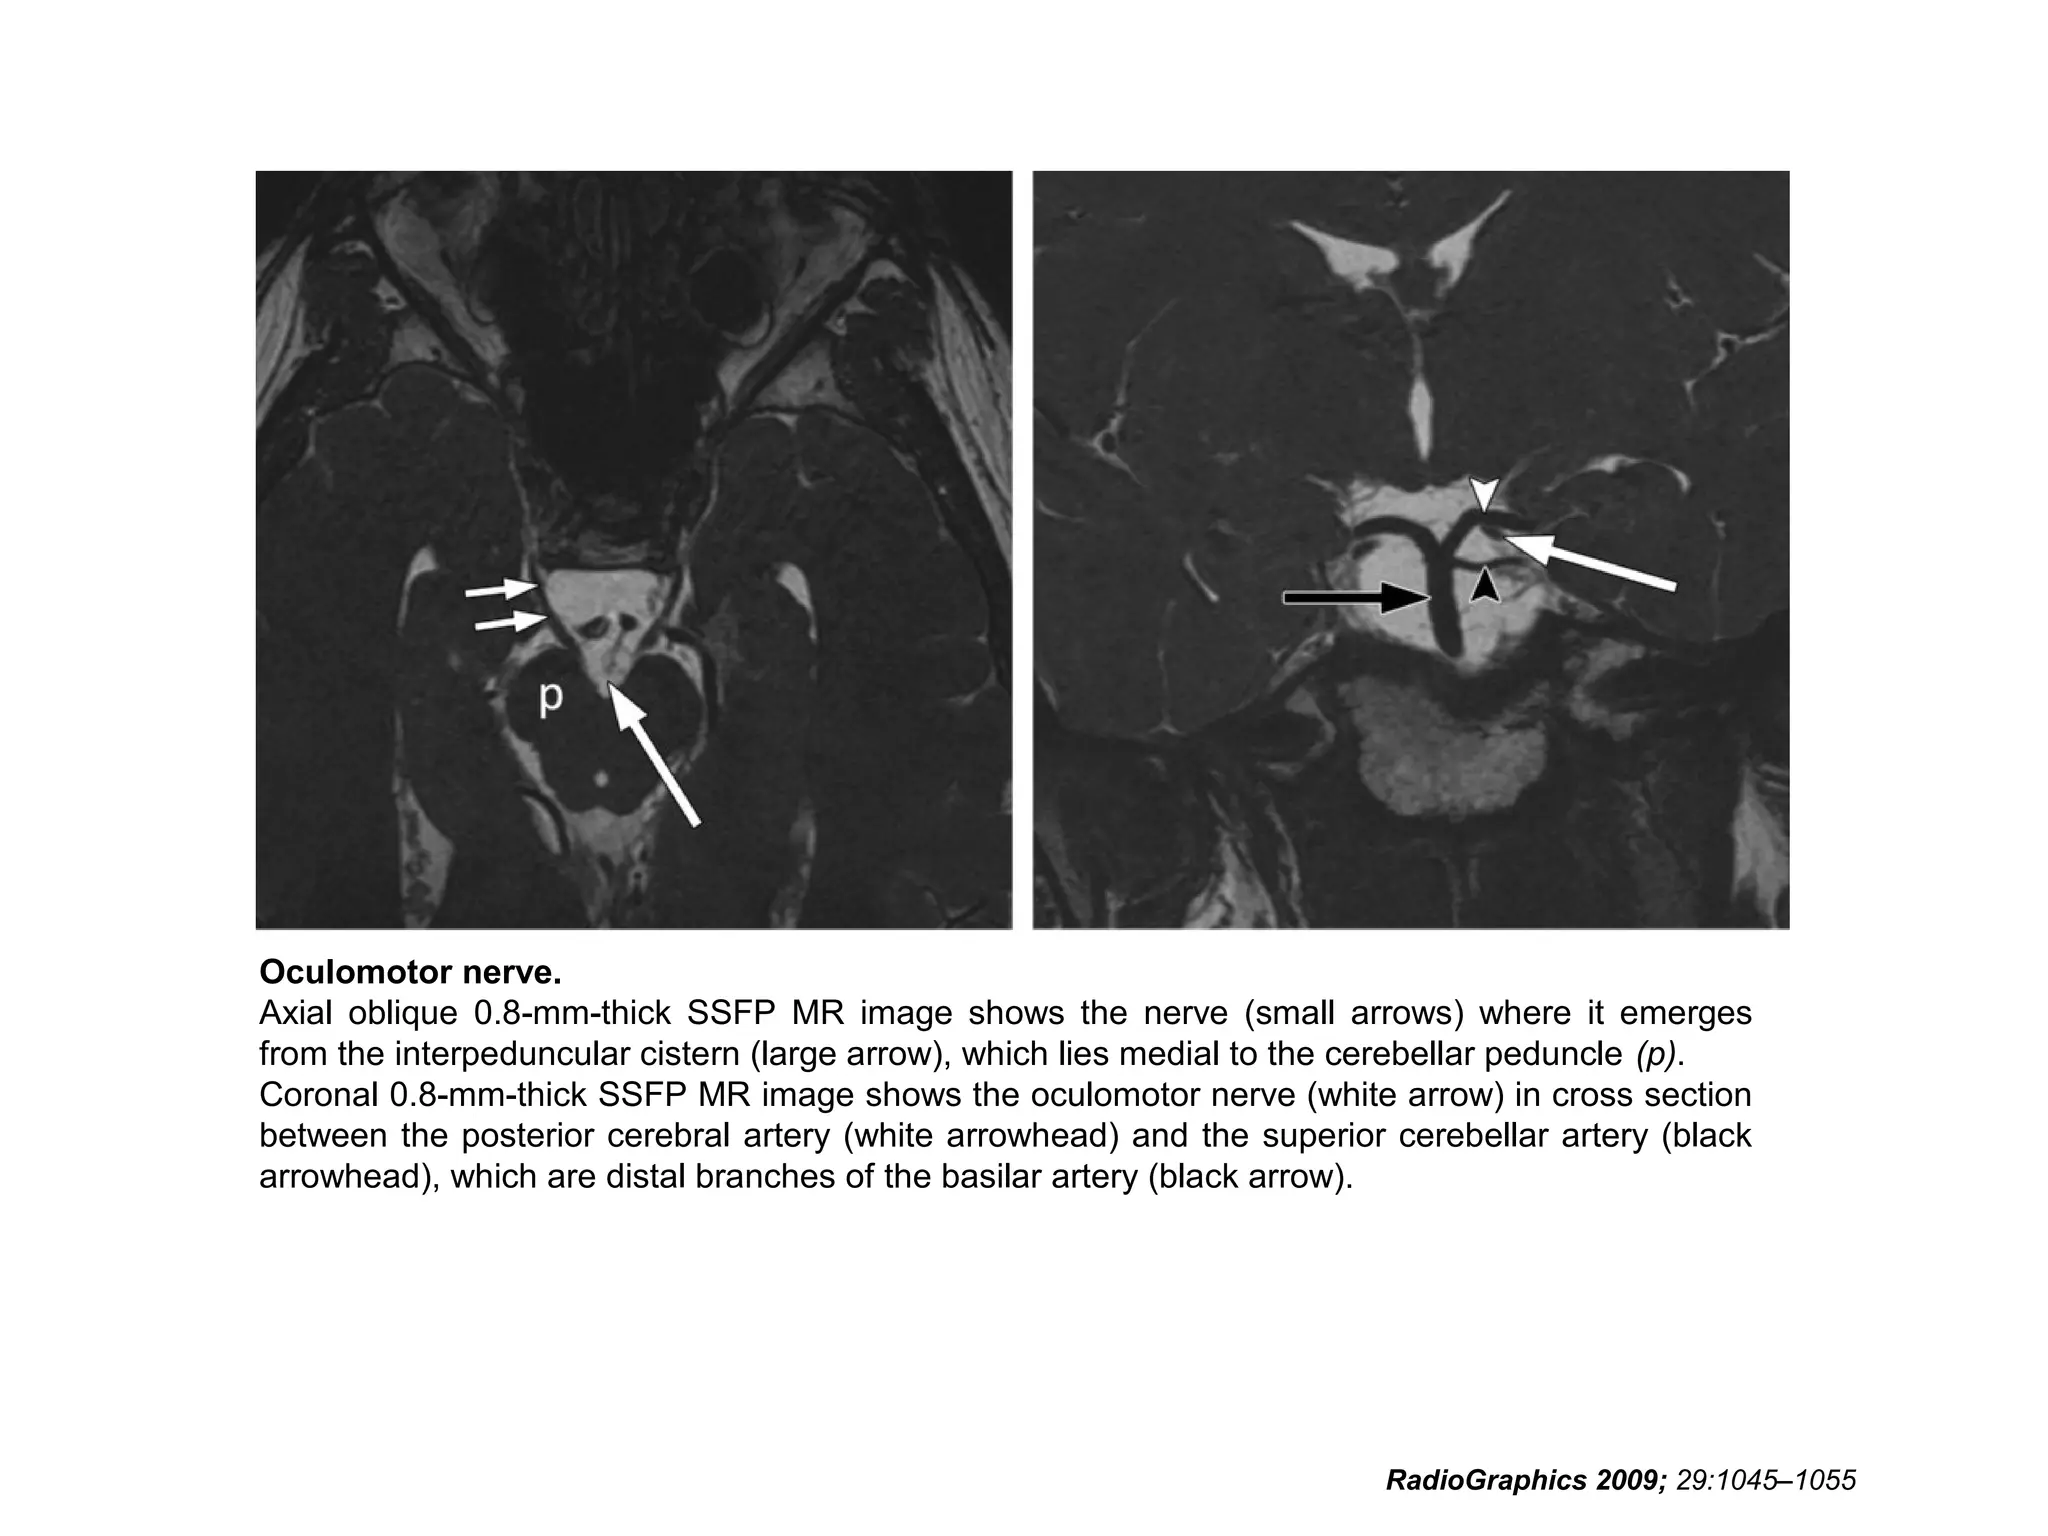

Oculomotor nerve.

Axial oblique 0.8-mm-thick SSFP MR image shows the nerve (small arrows) where it emerges

from the interpeduncular cistern (large arrow), which lies medial to the cerebellar peduncle (p).

Coronal 0.8-mm-thick SSFP MR image shows the oculomotor nerve (white arrow) in cross section

between the posterior cerebral artery (white arrowhead) and the superior cerebellar artery (black

arrowhead), which are distal branches of the basilar artery (black arrow).

RadioGraphics 2009; 29:1045–1055